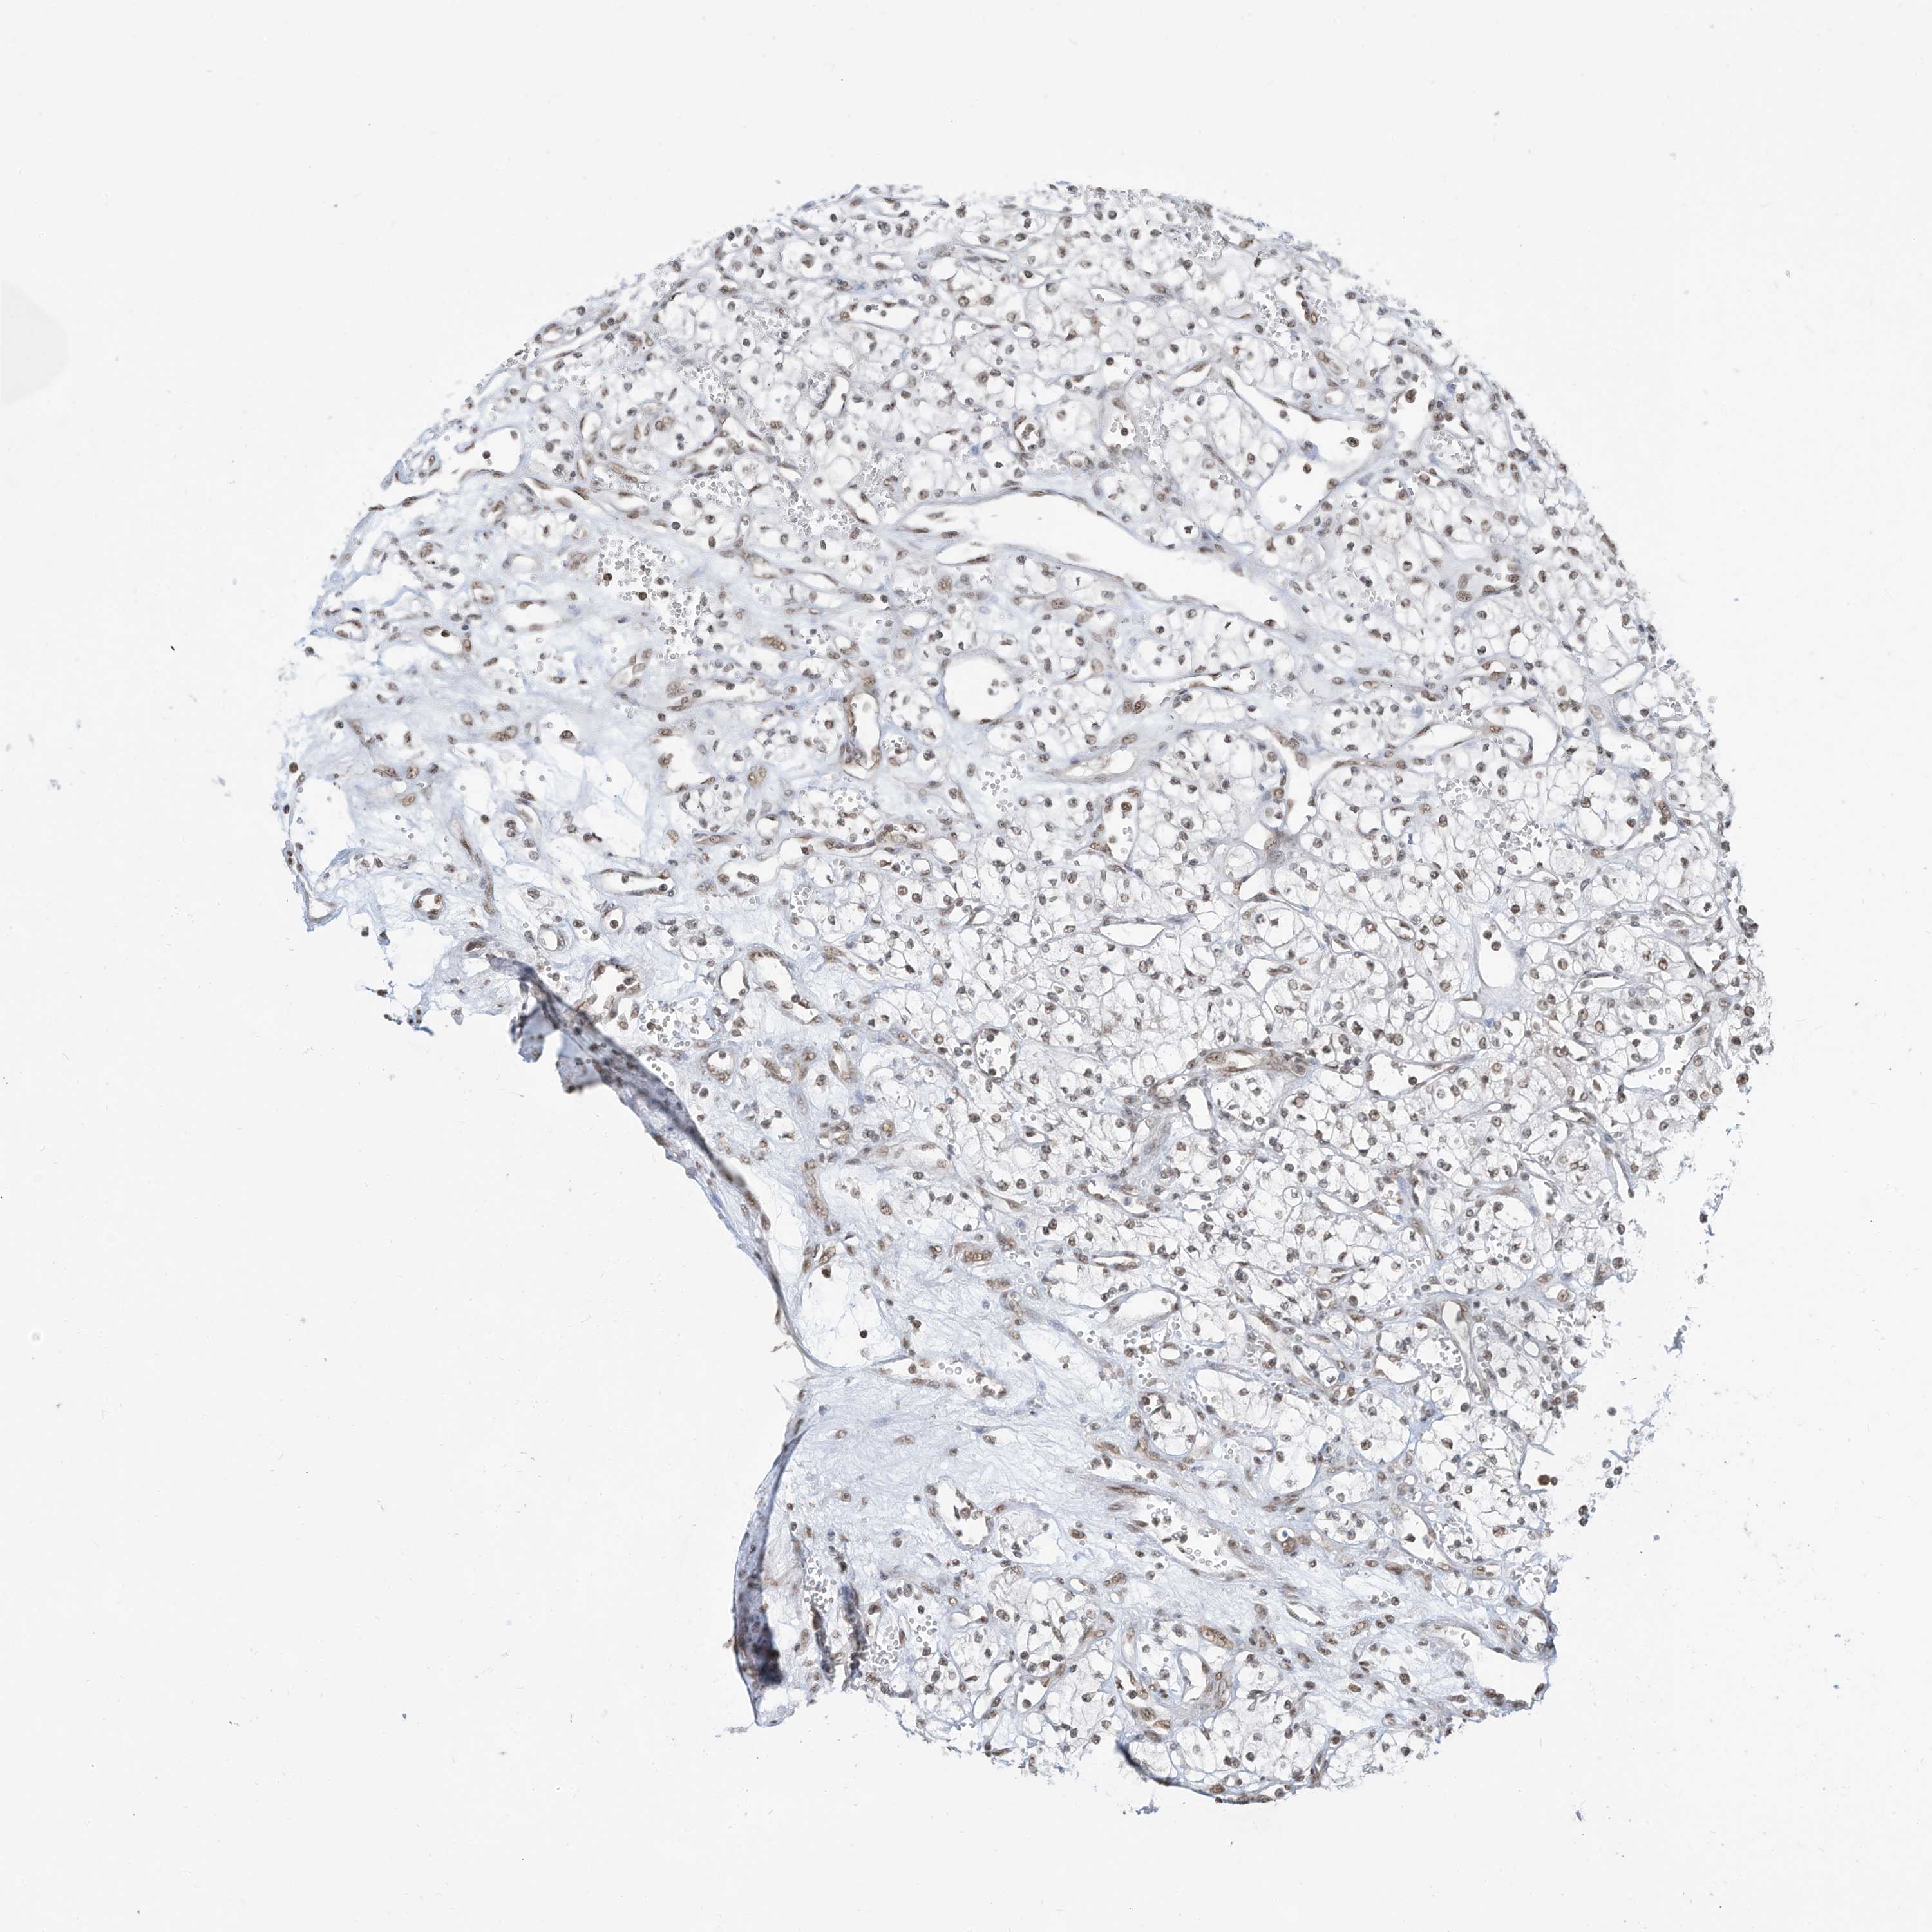

KIDNEY RENAL PAPILLARY CELL CARCINOMA (TCGA) - Interactive survival scatter ploti

The Survival Scatter plot shows the clinical status (i.e. dead or alive) for all individuals in the patient cohort, based on the same data that underlies the corresponding Kaplan-Meier plots. Patients that are alive at last time for follow-up are shown in blue and patients who have died during the study are shown in red.

The x-axis shows the expression levels (FPKM) of the investigated gene in the tumor tissue at the time of diagnosis. The y-axis shows the follow-up time after diagnosis (years). Both axes are complimented with kernel density curves demonstrating the data density over the axes. The top density plot shows the expression levels (FPKM) distribution among dead (red) and alive patients (blue). The right density plot shows the data density of the survived years of dead patients with high and low expression levels respectively, stratified using the cutoff indicated by the vertical dashed line through the Survival Scatter plot. This cutoff is automatically defined based on the FPKM cutoff that minimizes the p-score. The cutoff can be changed by dragging the vertical line or by entering a cutoff value in the square labeled "Current cut-off".

Under the Survival Scatter plot the p-score landscape (black curve; left axis) is shown together with dead median separation (red curve; right axis). Dead median separation is the difference in median mRNA expression between patients who have died with high and low expression, respectively. It is calculated as follows: median FPKM expression of dead patients with high expression - median FPKM expression of dead patients with low expression. This is intended to aid the user in visually exploring custom cutoffs and the associated p-scores and dead median separation.

Individual patient data is displayed and can be filtered by clicking on one or more of the category buttons on the top of the page. Categories describing expression level and patient information include: high, low, alive, dead, female, male and tumor stages. The scale of the x-axis can be toggled between linear and log-scale by clicking on the "x log" button. Mouse-over function shows TCGA ID, patient information and mRNA expression (FPKM) for each patient.

& Survival analysisi

Kaplan-Meier plots summarize results from analysis of correlation between mRNA expression level and patient survival. Patients were divided based on level of expression into one of the two groups "low" (under cut off) or "high" (over cut off). X-axis shows time for survival (years) and y-axis shows the probability of survival, where 1.0 corresponds to 100 percent.

ZNF195 is not prognostic in Kidney Renal Papillary Cell Carcinoma (TCGA)